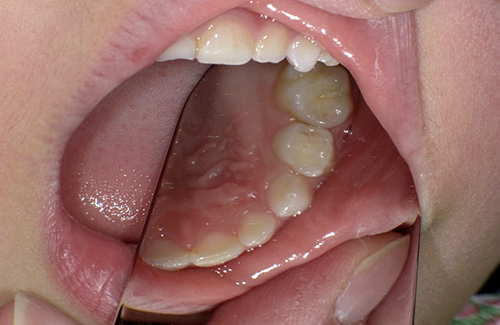

どこにむし歯があるのかな?

むし歯はないように

見えるけど…

ところが

レントゲンで見てみると…

矢印の黒い影がむし歯になっているところ